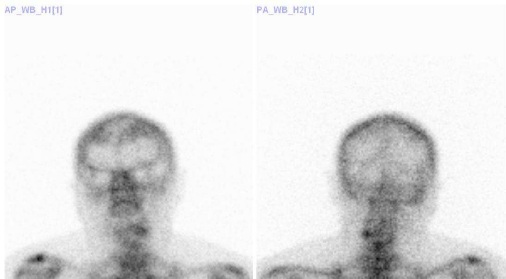

Na našem oddělení byly při scintigrafii skeletu v rel. krátkém období zachyceny nálezy

vyššího symetrického uptaku 99mTc-HDP (přípravek TechneScan

HDP firmy Mallinckrodt Medical) frontálně, bylo vysloveno podezření na frontální

hyperostózu. U všech případů byl tento nález potvrzen při RTG vyšetření lebky. Jednalo

se o pacientky ženy ve věku nad 60 let, vyšetřované z jiných důvodů. Viz.obr. č.1-5.

/ Obr.č. 1, pacientka č. 1, žena, 79 let/